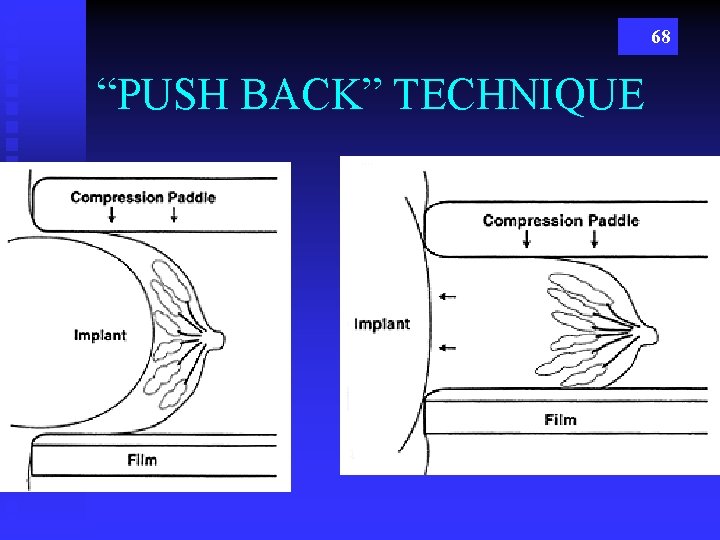

68 “PUSH BACK” TECHNIQUE